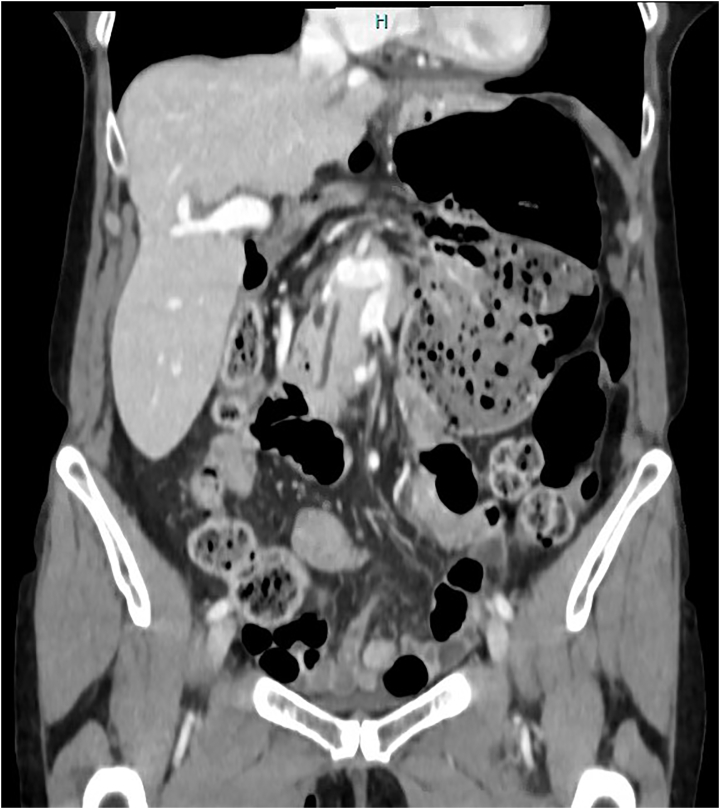

Fig. 2.

Coronal Ct scan showing colonic herniation through the Foramen of Winslow with dilated, stool-filled colon.